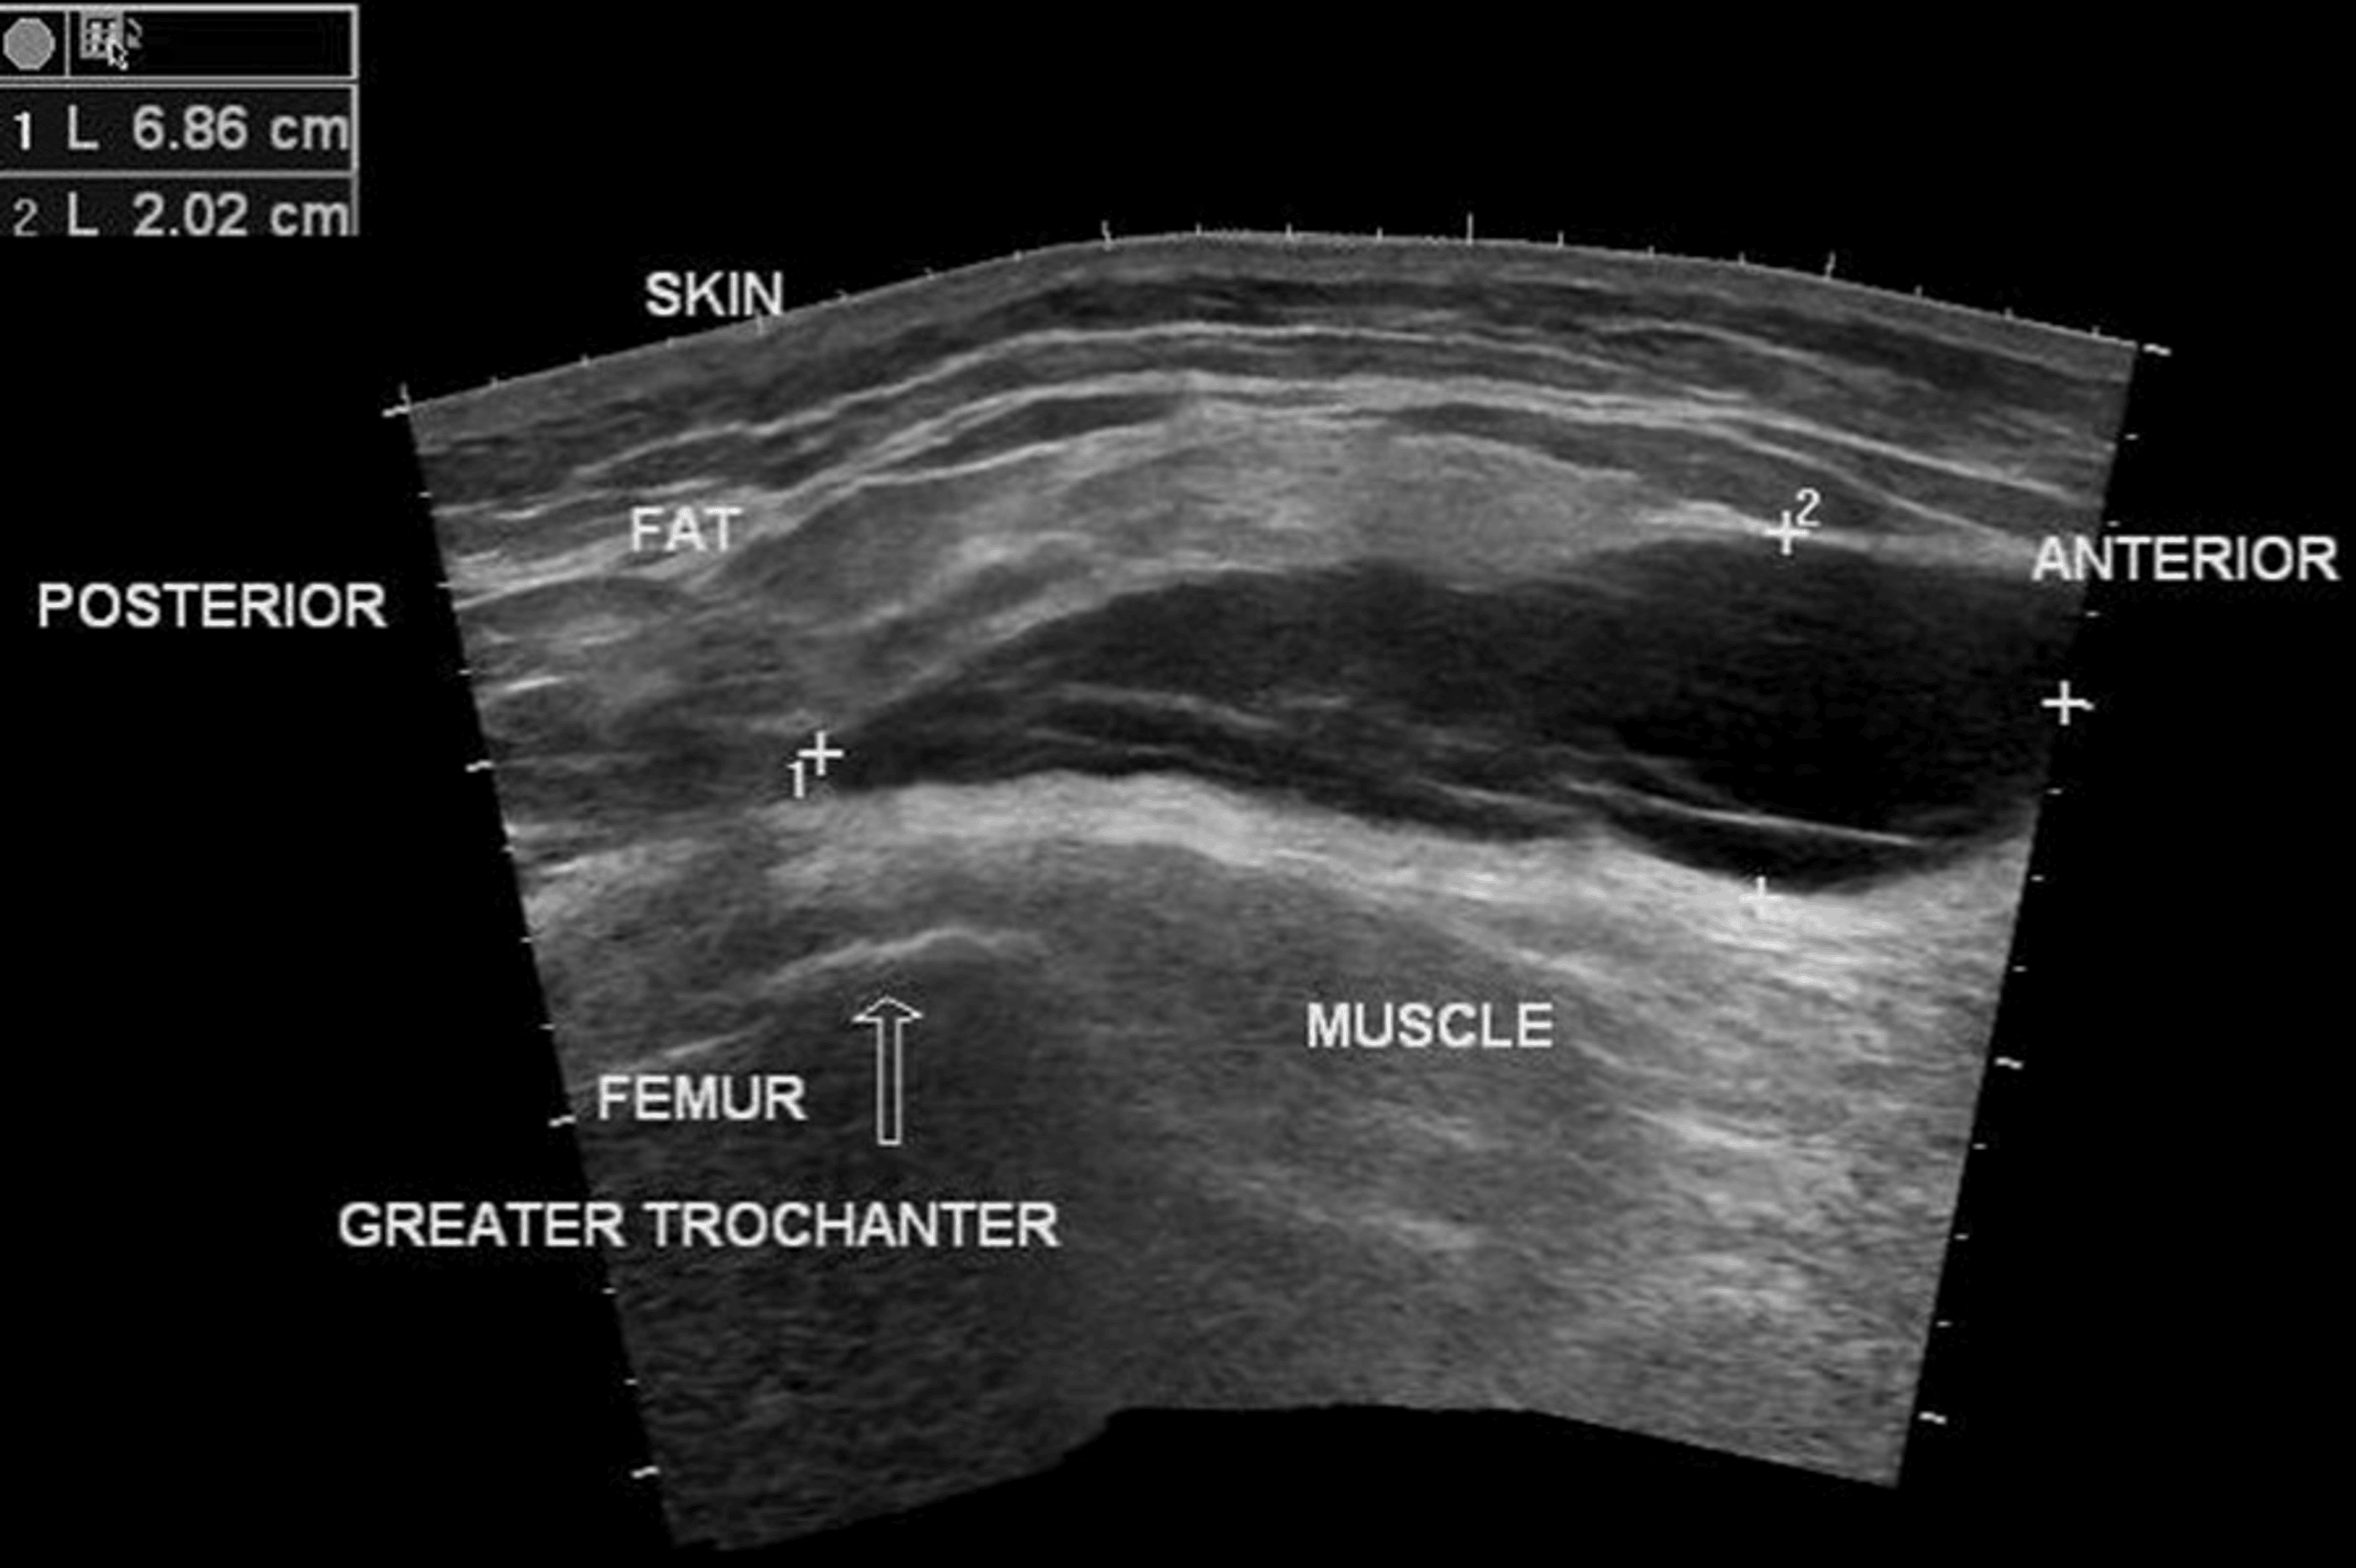

Morel Lavallee Lesion Ultrasound . Ultrasound, mri and ct scan can be used to diagnose mll. Mris are particularly important in the diagnosis of mll and help with differential diagnosis. Other ultrasound features may include the absence of flow on a colour doppler, and chronic lesions may show a hypoechoic capsule. Use of point of care. A, immediate postinjury changes can be seen in the soft tissues (asterisk) adjacent to a comminuted iliac wing in a. On ultrasound, the fluid mass is located anterior to the muscle but posterior to the hypodermis. On ultrasound, there is an elevation of the subcutaneous fat layer and superficial fascia layers from the deep fascia, causing a fluid collection, which is shown as an anechoic (dark) lesion.

Ultrasound, mri and ct scan can be used to diagnose mll. A, immediate postinjury changes can be seen in the soft tissues (asterisk) adjacent to a comminuted iliac wing in a. Mris are particularly important in the diagnosis of mll and help with differential diagnosis. Use of point of care. Other ultrasound features may include the absence of flow on a colour doppler, and chronic lesions may show a hypoechoic capsule. On ultrasound, the fluid mass is located anterior to the muscle but posterior to the hypodermis. On ultrasound, there is an elevation of the subcutaneous fat layer and superficial fascia layers from the deep fascia, causing a fluid collection, which is shown as an anechoic (dark) lesion.